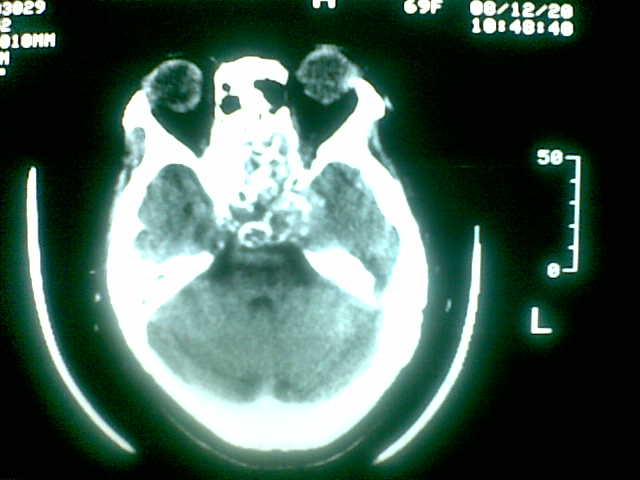

69岁 女 主因头痛就诊。大家看看起源于哪里啊

起源于斜坡,考虑脊索瘤.

起源于斜坡,考虑脊索瘤. 很典型

考虑脊索瘤(起源于蝶枕联合部)。

颅底骨质破坏伴软组织密度影、斑片状高密度(死骨影)。

考虑:脊索瘤。

多为脊索瘤。起源于斜坡!